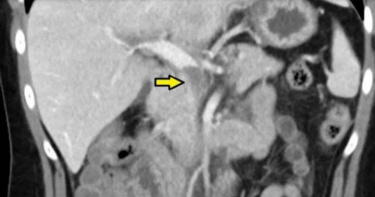

55歲高先生過去有腎結石病史,日前出現腰背痛,以為是結石復發,到醫院做影像檢查卻發現是腹部一顆8公分大的腹主動脈瘤在作怪。因為高先生年紀相對年輕,起初建議選擇傳統的開腹手術將主動脈換成人工血管,但卻在急診發生心絞痛。爲避免併發心肌梗塞,醫師以微創手術替病人置放難度較高且臨床較少使用的T分枝主動脈支架,再於術後十四天執行冠狀動脈繞道手術,同時解除主動脈瘤破裂和心肌梗塞的危機。腹主動脈瘤初期無症狀 破裂後的未手術死亡率達100%主動脈是供應人體血流的主要大血管,依部位可分為胸主動脈跟腹主動脈,當血管壁因疾病或老化退化變形、變薄或膨出,就會形成主動脈瘤。台北慈濟醫院心臟血管外楊凱文醫師指出,男性的發生率是女性的四至五倍,年紀越大、發生率越高,大於65歲的男性約有5-8%的人有腹主動脈瘤,其餘則是好發在抽菸、三高控制不良、其他心血管疾病或家族史的人。腹主動脈瘤除非是大到壓迫其他器官組織,或是已經破裂和即將破裂才會出現症狀,且症狀皆不明確,從肚子痛、腰痛、鼠蹊部痛到大腿痛都有可能,因此容易跟類似疾病混淆而延遲診斷。若是破裂則會大出血,此時未手術的死亡率將高達100%,即便手術死亡率也高達50%,可以說是人體的隱形炸彈。這些情況需須積極治療 多以支架置放治療為主根據國際治療準則,女性5公分以上的腹主動脈瘤或男性5.5公分以上就必須積極治療,以免增加破裂風險。目前腹主動脈瘤多以傷口小、治療跟恢復速度快的支架置放為主流治療方式,但僅限於離附近重要血管間尚有一段距離的腹主動脈瘤。T分枝主動脈支架非新技術,特點是上面有許多孔洞,不會擋住重要血流,但因置放過程相對複雜且傳統主動脈支架和傳統手術同時無法施行的案例不多,所以臨床實際使用此技術的案例較少。動脈瘤是心血管疾病之一 控制三高與戒菸遠離疾病風險楊凱文醫師提醒民眾,所有心血管疾病的危險因子都相同,高危險族群建議戒菸並將三高控制好,若曾在檢查中發現動脈瘤,務必定期回診追蹤確認是否變大,及早發現與治療。